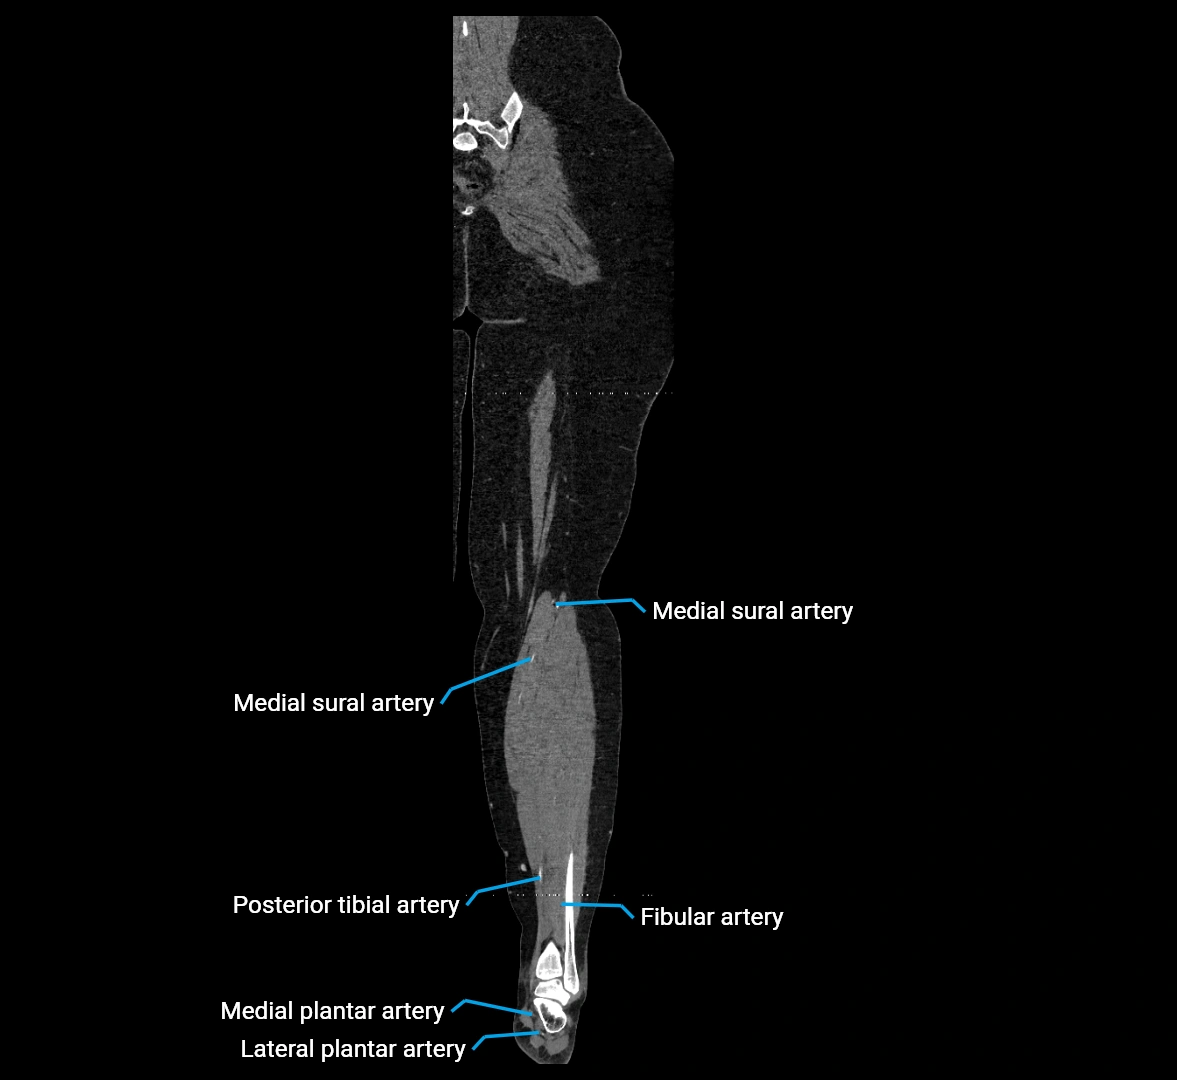

CT Appearance

Non-contrast CT:

• Appears as a tubular soft tissue structure anterior to vertebral bodies

• Calcified atherosclerotic plaques appear as hyperdense foci along the wall

• Useful for screening abdominal aortic aneurysm (AAA) size and mural calcification

Contrast-enhanced CT (CTA):

• Gold standard for abdominal aortic imaging

• Provides excellent detail of lumen, wall, aneurysm, thrombus, and branch vessels

• Multiplanar and 3D reconstructions help in aneurysm measurement, stent graft planning, and dissection evaluation

• Detects acute rupture, traumatic injury, or occlusion with high sensitivity